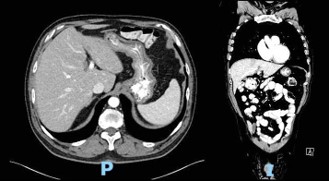

Computed Tomography (CT) scan performed at the time of admission revealed abundant food content with organized appearance in the abdomen (Figure 1), which was morphologically similar to that observed in previous CT scans. The findings supported chronic food retention with difficulty in gastric emptying at the level of pyloric antrum. Pharyngo-esophageal study revealed the presence of a bezoar occupying the entire gastric chamber with normal esophageal motility (Figure 2).

Figure 2: Pharyngo-esophageal study.